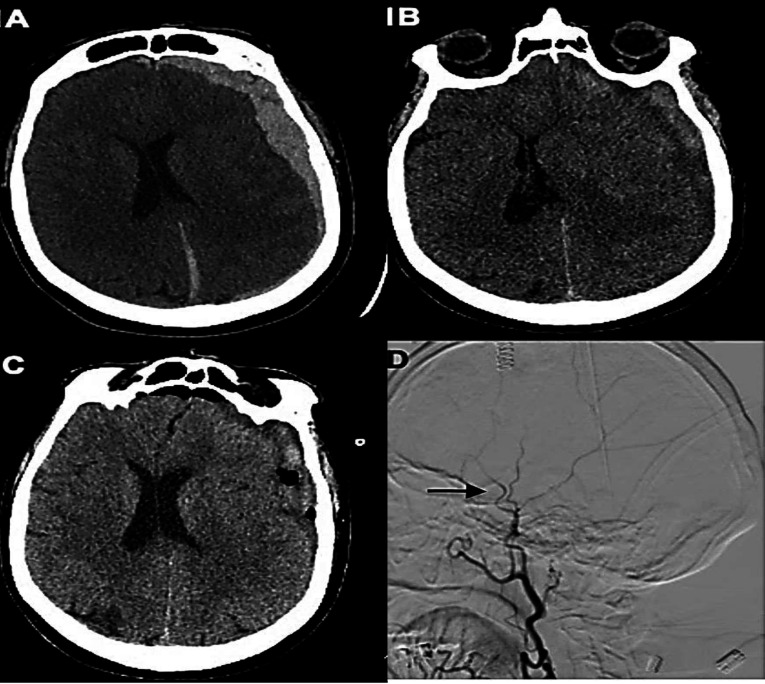

Acute subdural haemorrhage in a warfarin user following leech bite: Clinical note and review.